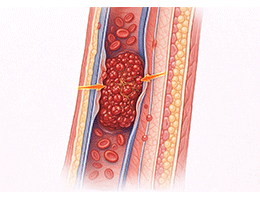

혈전증 (Thrombosis)

폐색전증 (Pulmonary Embolism)

심부정맥혈전증 (Deep Vein Thrombosis)